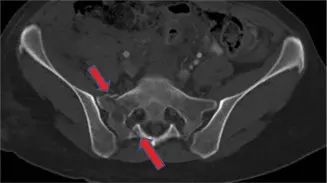

## مقدمة حول كسور العجز كسور العجز هي إصابات خطيرة تصيب عظم العجز، وهو عظم كبير مثلث الشكل يقع في قاعدة العمود الفقري، بين الفقرات القطنية والحوض. يلعب العجز دورًا حاسمًا في نقل وزن الجسم من العمود الفقري إلى الحوض والساقين، ويوفر الحماية للعديد من الأعصاب الهامة التي تتحكم في وظائف الأطراف السفلية والمثانة والأمعاء والوظيفة الجنسية. تتراوح كسور العجز في شدتها من كسور بسيطة غير مسببة للنزوح إلى كسور معقدة ومزاحة قد تؤدي إلى عدم استقرار الحوض أو إصابات عصبية خطيرة. يمكن أن تحدث هذه الكسور نتيجة لصدمات عالية الطاقة مثل حوادث السيارات أو السقوط من ارتفاع، أو بسبب صدمات خفيفة لدى كبار السن الذين يعانون من هشاشة العظام. إن التشخيص الدقيق والعلاج الفعال لكسور العجز أمر بالغ الأهمية لتجنب المضاعفات طويلة الأمد، مثل الألم المزمن، عدم استقرار الحوض، أو الخلل العصبي. يتطلب هذا النوع من الإصابات نهجًا متخصصًا يجمع بين الفهم العميق للتشريح، والخبرة في تقنيات التصوير المتقدمة، والمهارة في الخيارات العلاجية، سواء كانت تحفظية أو جراحية. يُعرف الأستاذ الدكتور محمد هطيف في صنعاء بخبرته الواسعة وتميزه في إدارة كسور العجز، حيث يتبع أحدث البروتوكولات العلاجية ويستخدم التقنيات الجراحية المتقدمة لضمان أفضل النتائج لمرضاه. ## التشريح المعقد لعظم العجز لفهم كسور العجز بشكل كامل، من الضروري أن يكون لدينا فهم واضح لتشريح هذا العظم الفريد وموقعه ضمن الهيكل العظمي. ### موقع ووظيفة عظم العجز عظم العجز هو عظم مثلثي كبير يتكون من خمس فقرات عجزية (S1-S5) تندمج معًا في مرحلة البلوغ. يقع العجز بين الفقرة القطنية الخامسة (L5) وعظم العصعص، ويتمفصل مع عظمي الحرقفة (الإيليوم) على الجانبين لتكوين المفاصل العجزية الحرقفية (SI joints)، والتي تُعد مفاتيح استقرار الحوض. **الوظائف الرئيسية للعجز تشمل:** * **نقل الوزن:** يعمل كجسر لنقل وزن الجسم من العمود الفقري إلى الطرفين السفليين. * **الدعم والاستقرار:** يوفر الدعم الهيكلي للحوض والعمود الفقري. * **حماية الأعصاب:** يحتوي على قناة عجزية تمر من خلالها جذور الأعصاب العجزية التي تغذي الأطراف السفلية، المثانة، الأمعاء، والأعضاء التناسلية. ### القناة العجزية والأعصاب تُعد القناة العجزية امتدادًا للقناة الشوكية، وتحتوي على الضفيرة العجزية التي تتفرع منها أعصاب مهمة مثل العصب الوركي. تمر الأعصاب عبر الثقوب العجزية (foramina) على جانبي العجز. أي كسر في العجز يمكن أن يؤثر بشكل مباشر على هذه الأعصاب، مما يؤدي إلى أعراض عصبية متنوعة. ### تصنيف دينيس لكسور العجز يُعد تصنيف دينيس (Denis Classification) الأكثر استخدامًا لتقييم كسور العجز، ويعتمد على موقع خط الكسر بالنسبة للثقوب العجزية: * **النوع الأول (Denis Type I):** كسور تقع جانبيًا (بعيدًا) عن الثقوب العجزية. * **معدل الإصابة العصبية:** حوالي 6%. * **الخصائص:** عادة ما تكون هذه الكسور مستقرة نسبيًا، ولكن قد تؤثر على الأربطة العجزية الحرقفية. * **النوع الثاني (Denis Type II):** كسور تمر عبر الثقوب العجزية. * **معدل الإصابة العصبية:** حوالي 28%. * **الخصائص:** تُعد هذه الكسور أكثر عرضة لإصابة الأعصاب التي تمر عبر الثقوب، مما قد يؤدي إلى أعراض عصبية في الأطراف السفلية. * **النوع الثالث (Denis Type III):** كسور تقع وسطيًا (باتجاه الخط الأوسط) للثقوب العجزية، وغالبًا ما تشمل القناة العجزية نفسها. * **معدل الإصابة العصبية:** حوالي 57%. * **الخصائص:** تُعد هذه الكسور الأكثر خطورة من حيث المضاعفات العصبية، حيث يمكن أن تؤثر بشكل مباشر على جذور الأعصاب في القناة العجزية، مما يسبب خللاً في وظائف المثانة والأمعاء والوظيفة الجنسية. إن فهم هذا التصنيف ضروري لـ الأستاذ الدكتور محمد هطيف لتحديد خطة العلاج الأنسب بناءً على نوع الكسر ومخاطر الإصابة العصبية المصاحبة. ## الأسباب وعوامل الخطر لكسور العجز يمكن أن تحدث كسور العجز نتيجة لمجموعة متنوعة من الأسباب، وتزداد احتمالية حدوثها بوجود عوامل خطر معينة. ### أسباب كسور العجز 1. **الصدمات عالية الطاقة:** * **حوادث السيارات:** هي السبب الأكثر شيوعًا لكسور العجز المعقدة، خاصةً عندما تكون قوى الاصطدام شديدة. * **السقوط من ارتفاع:** يمكن أن يؤدي السقوط من ارتفاعات كبيرة إلى إصابات شديدة في الحوض والعجز. * **الإصابات الرياضية:** في بعض الرياضات عالية التأثير، قد تحدث كسور العجز. 2. **الصدمات منخفضة الطاقة (لدى كبار السن):** * **السقوط البسيط:** حتى السقوط من وضعية الوقوف يمكن أن يسبب كسورًا في العجز لدى الأشخاص الذين يعانون من هشاشة العظام. 3. **كسور الإجهاد (Stress Fractures):** * تحدث هذه الكسور نتيجة للإجهاد المتكرر على العظم، وغالبًا ما تُرى في الرياضيين أو الأفراد الذين يمارسون أنشطة بدنية شاقة بشكل متكرر. 4. **الأورام:** * يمكن أن تؤدي الأورام الأولية أو الثانوية (النقائل) في العجز إلى إضعاف العظم وزيادة خطر الكسر. 5. **العدوى:** * الالتهابات التي تصيب عظم العجز يمكن أن تضعفه وتجعله عرضة للكسر. ### عوامل الخطر 1. **هشاشة العظام:** * تُعد هشاشة العظام، وهي حالة تتميز بنقص كثافة العظام، عامل الخطر الرئيسي لكسور العجز الناتجة عن صدمات منخفضة الطاقة، خاصة لدى النساء بعد انقطاع الطمث وكبار السن. 2. **العمر:** * يزداد خطر الإصابة بكسور العجز مع التقدم في العمر، ويرجع ذلك جزئيًا إلى زيادة معدل السقوط وتفشي هشاشة العظام. 3. **الجنس:** * النساء أكثر عرضة للإصابة بهشاشة العظام وبالتالي كسور العجز، خاصة بعد انقطاع الطمث. 4. **نقص فيتامين د والكالسيوم:** * يؤثر نقص هذه العناصر الغذائية الأساسية على صحة العظام وكثافتها. 5. **بعض الحالات الطبية:** * أمراض مثل التهاب المفاصل الروماتويدي، وبعض أمراض الغدد الصماء، والاضطرابات التي تؤثر على امتصاص العناصر الغذائية يمكن أن تزيد من خطر الكسور. 6. **الأدوية:** * الاستخدام طويل الأمد لبعض الأدوية مثل الكورتيكوستيرويدات يمكن أن يضعف العظام. 7. **نمط الحياة:** * قلة النشاط البدني، التدخين، والإفراط في استهلاك الكحول يمكن أن تؤثر سلبًا على صحة العظام. يُولي الأستاذ الدكتور محمد هطيف اهتمامًا خاصًا بتقييم عوامل الخطر لدى كل مريض، مما يساعد في وضع خطة علاجية وقائية ومخصصة لتقليل فرص حدوث كسور مستقبلية. ## الأعراض والعلامات لكسور العجز تتنوع أعراض كسور العجز اعتمادًا على شدة الكسر وموقعه، وما إذا كانت هناك إصابة عصبية مصاحبة. من المهم التعرف على هذه الأعراض لطلب المساعدة الطبية في الوقت المناسب. ### الأعراض الشائعة 1. **الألم:** * **ألم أسفل الظهر:** يُعد الألم في منطقة أسفل الظهر والأرداف هو العرض الأكثر شيوعًا. * **ألم ينتشر إلى الساقين:** يمكن أن ينتشر الألم إلى الفخذين أو الساقين أو القدمين، خاصةً إذا كانت هناك إصابة للأعصاب. * **ألم يزداد بالحركة:** يزداد الألم عادةً عند الوقوف، المشي، الجلوس، أو أي حركة تضع ضغطًا على الحوض أو أسفل الظهر. * **ألم عند لمس المنطقة:** قد تكون المنطقة فوق العجز مؤلمة عند اللمس أو الضغط. 2. **تورم وكدمات:** * في بعض الحالات، خاصة بعد الصدمات الشديدة، قد يلاحظ المريض تورمًا أو كدمات في منطقة أسفل الظهر أو الأرداف. 3. **صعوبة في المشي أو الوقوف:** * قد يجد المريض صعوبة في تحمل الوزن على الساقين أو المشي بشكل طبيعي بسبب الألم أو عدم استقرار الحوض. ### الأعراض العصبية نظرًا لقرب عظم العجز من العديد من الأعصاب الحيوية، فإن الإصابة العصبية هي إحدى المضاعفات المحتملة والخطيرة لكسور العجز. يمكن أن تشمل الأعراض العصبية ما يلي: 1. **خدر أو تنميل:** * قد يشعر المريض بخدر أو تنميل في منطقة الأرداف، العجان (المنطقة بين الأعضاء التناسلية والشرج)، أو الأطراف السفلية. 2. **ضعف العضلات:** * ضعف في عضلات الساقين أو القدمين، مما قد يؤثر على القدرة على رفع القدم (foot drop) أو المشي. 3. **خلل في وظائف المثانة والأمعاء:** * فقدان السيطرة على المثانة (سلس البول) أو الأمعاء (سلس البراز). * صعوبة في التبول أو التبرز. * احتباس البول أو الإمساك الشديد. 4. **خلل جنسي:** * قد يعاني المرضى من مشاكل في الوظيفة الجنسية. 5. **متلازمة ذيل الفرس (Cauda Equina Syndrome):** * في الحالات الشديدة، يمكن أن يؤدي الضغط على الأعصاب في القناة العجزية إلى متلازمة ذيل الفرس، وهي حالة طارئة تتطلب تدخلًا جراحيًا فوريًا. تشمل أعراضها ألمًا شديدًا في الظهر والساقين، خدرًا في منطقة السرج (perineum)، وضعفًا شديدًا في الساقين، وخللاً في وظائف المثانة والأمعاء. يُعد التقييم السريع والدقيق للأعراض العصبية أمرًا بالغ الأهمية، و الأستاذ الدكتور محمد هطيف مجهز بالخبرة اللازمة لإجراء هذا التقييم وتحديد الحاجة إلى التدخل العاجل. ## التشخيص الدقيق لكسور العجز يتطلب التشخيص الدقيق لكسور العجز مزيجًا من التاريخ المرضي المفصل، الفحص السريري الشامل، وتقنيات التصوير المتقدمة. يهدف التشخيص إلى تحديد موقع الكسر، نوعه، مدى نزوح العظام، ووجود أي إصابات عصبية. ### الفحص السريري يبدأ الأستاذ الدكتور محمد هطيف بتقييم شامل يتضمن: 1. **التاريخ المرضي:** جمع معلومات حول كيفية حدوث الإصابة، الأعراض التي يعاني منها المريض (الألم، الخدر، الضعف)، وجود أي أمراض مزمنة (مثل هشاشة العظام)، وتناول الأدوية. 2. **فحص الجهاز العصبي:** تقييم وظيفة الأعصاب في الأطراف السفلية، بما في ذلك قوة العضلات، الإحساس، والمنعكسات. يُعد هذا الفحص حاسمًا للكشف عن أي إصابة عصبية محتملة. 3. **فحص وظائف المثانة والأمعاء:** سؤال المريض عن أي تغييرات في التحكم في المثانة أو الأمعاء. 4. **فحص منطقة العجز:** البحث عن أي تورم، كدمات، أو تشوهات واضحة في منطقة العجز. ### تقنيات التصوير تُعد الأشعة التصويرية ضرورية لتأكيد تشخيص كسر العجز وتحديد خصائصه بدقة. 1. **الأشعة السينية (X-rays):** * تُعد الأشعة السينية الخطوة الأولى في التصوير، ويمكن أن تظهر الكسور الواضحة في العجز. ومع ذلك، قد لا تكون كسور العجز دائمًا واضحة على الأشعة السينية التقليدية، خاصة الكسور غير المزاحة أو كسور الإجهاد. * **مناظر الحوض المختلفة:** تُستخدم مناظر معينة للحوض (مثل منظر المدخل ومنظر المخرج) لتقييم استقرار الحوض وتحديد مدى النزوح. 2. **التصوير المقطعي المحوسب (CT Scan):** * يُعد التصوير المقطعي المحوسب الأداة الأكثر قيمة لتشخيص كسور العجز. يوفر صورًا ثلاثية الأبعاد مفصلة للعظم، مما يسمح لـ الأستاذ الدكتور محمد هطيف بتحديد: * الموقع الدقيق للكسر. * نوع الكسر (مثل تصنيف دينيس). * مدى النزوح. * وجود أي شظايا عظمية قد تضغط على الأعصاب. * تقييم دقيق لتشوهات العجز (Sacral Dysmorphism). كسور العظام المعقدة وإصابات الحوادث ليس قدراً محتوماً! التشخيص الدقيق والعلاج المتخصص يمكن أن يعيد لك كامل وظيفتك وحريتك في الحركة بدون ألم.